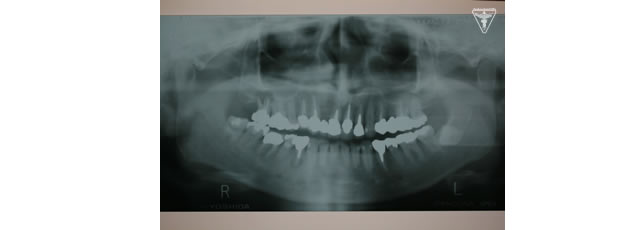

また、レントゲンから抜歯しなければならない歯や根に病巣を持っている歯が確認できる。

根破折の為抜歯、審美的に抜いた部位が陥没しない様に処置しました。

抜歯後、歯周病処置、歯内療法処置、咬合高径改善、プロビジュナルレストレーションを経て最終補綴をおこないました。

初期治療を経て歯周外科、歯内療法により病巣の消失が認められ改善された。

右上は将来人工歯根による処置の為GBRを行った。